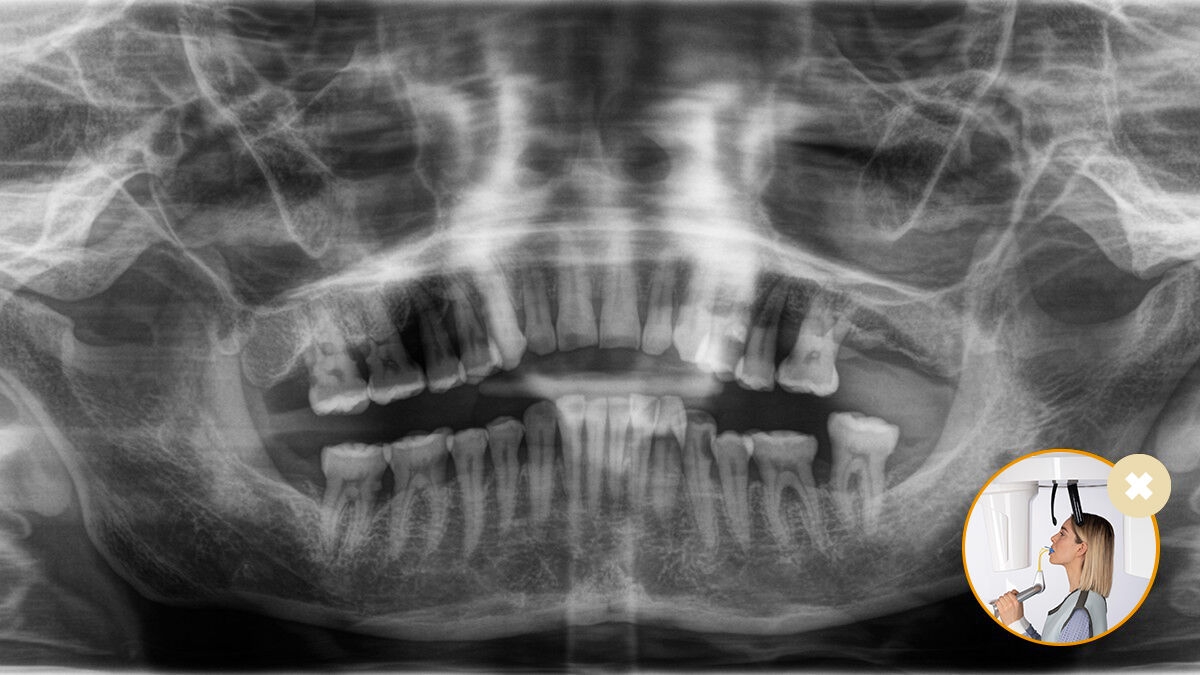

Correct patient positioning leads to high image quality to support an accurate diagnosis and facilitates an improved patient experience.

This is our 10-point concept for easy patient positioning and X-ray imaging. It is primarily about two things: high image quality and comfort for the patient and the assistant.

Correct patient positioning with the occlusal bite block ‒ guaranteed ideal inclination for panoramic images